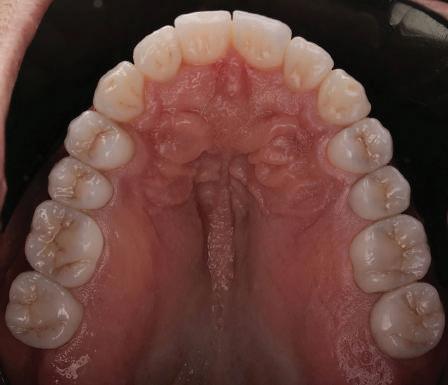

11Dental Tribune Bulgarian Edition / октомври 2022 г. Преди лечението Фиг. 1 Фиг. 2 Фиг. 3 Фиг. 4 Фиг. 5 Фиг. 6 Фиг. 7 Фиг. 9 Фиг. 10 Фиг. 11 Фиг. 8 Фиг. 12 Фиг. 13

12 Dental Tribune Bulgarian Edition / октомври 2022 г. По време на лечението Фиг. 14 Фиг. 16 Фиг. 20 Фиг. 23 Фиг. 21 Фиг. 24 Фиг. 26 Фиг. 28 Фиг. 31 Фиг. 34 Фиг. 29 Фиг. 32 Фиг. 35 Фиг. 30 Фиг. 33 Фиг. 36 Фиг. 27 Фиг. 22 Фиг. 25 Фиг. 17 Фиг. 18 Фиг. 19 Фиг. 15

13Dental Tribune Bulgarian Edition / октомври 2022 г. След лечението За авторите: Д-р Калин Маринов е специалист в областта на имплантологията, протетиката и естетичната хирургия. Завършил е дентална медици на в София през 2012 г. През 2014 г. основава Sky Dental Clinic. Бил е на обмен ни начала в катедра „Протетика“ на Университета по дентална медицина във Фрайбург, Германия. Живял е и е практикувал в Мелбърн, Австралия, и е посеща вал курсове и лекции в Италия, Швейцария, Германия с насоченост в естетич ната хирургия и имплантология, както и тоталната рехабилитация на устна та кухина чрез импланти. Зт. Стефан Петров основава собствена лаборатория през 2006 г. Официален демонстратор на GC за България, като от 2015 г. е KOL за Източна Европа. Инструктор е на Straumann за България. Лаборатория та му има сертификат за пилотна лаборатория на Micerium – Италия. Носител е на множество награди в денталния конкурс „Усмивка на годината”. Носител е на награда CERAMISTS MASTER CUP с д-р Софиен Риахи в престижния международен конгрес CERAMISTS – NO LIMITS 2015 г. Изнася лекции и провежда курсове в редица европейски страни. Фиг. 37 Фиг. 40 Фиг. 43 Фиг. 45 Фиг. 47 Фиг. 50 Фиг. 48 Фиг. 49 Фиг. 41 Фиг. 44 Фиг. 46 Фиг. 42 Фиг. 38 Фиг. 39